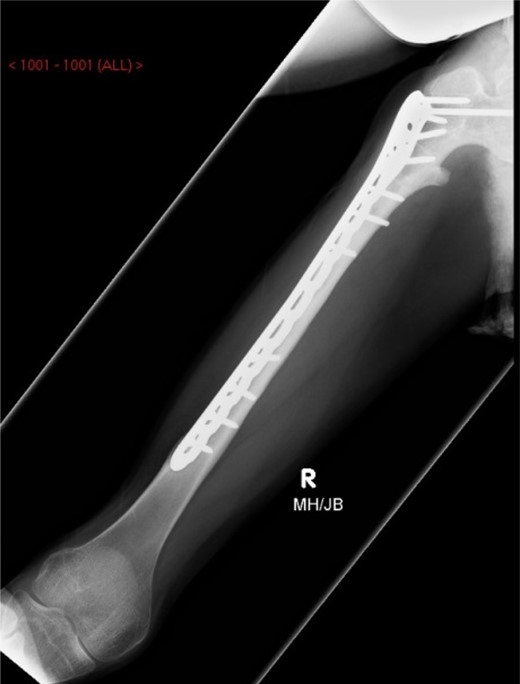

Under general anaesthesia, open reduction and internal fixation using a 10 hole philos plate was performed with the patient in a supine position on the traction table utilizing a lateral approach. Using C-arm image intensification, the height of the plate was judged, then applied to the bone and secured both proximally and distally to the fracture with proximal locking screws inserted where possible (Fig. 2a–c). Securing the cephalic segment of the philos plate to the proximal femur proved challenging due to the femoral neck defect left by the removal of the blade plate. Final reduction was judged to be near anatomical with the wound thoroughly irrigated with saline before closure. Post-operative treatment included IV antibiotics with mobility instructions unnecessary due to the patient's non-ambulatory status. The patient was discharged after 5 days with a follow-up period over 11 months. There were no post-operative complications during this time and radiographs showed an anatomically healed fracture (Fig. 3).

Image intensifier intra-operative AP highlighting 10 hole PHILOS applied with near anatomical reduction (a–c).